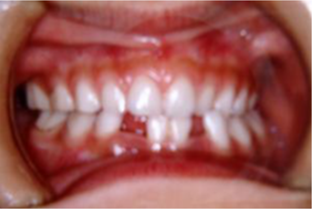

乳歯で早めに治した方がいい場合・・・犬歯から奥歯が反対咬合になっている時

自然には治らず、正中がずれ、お顔が曲がってきます。

上あごの成長が非対称に妨げられます。